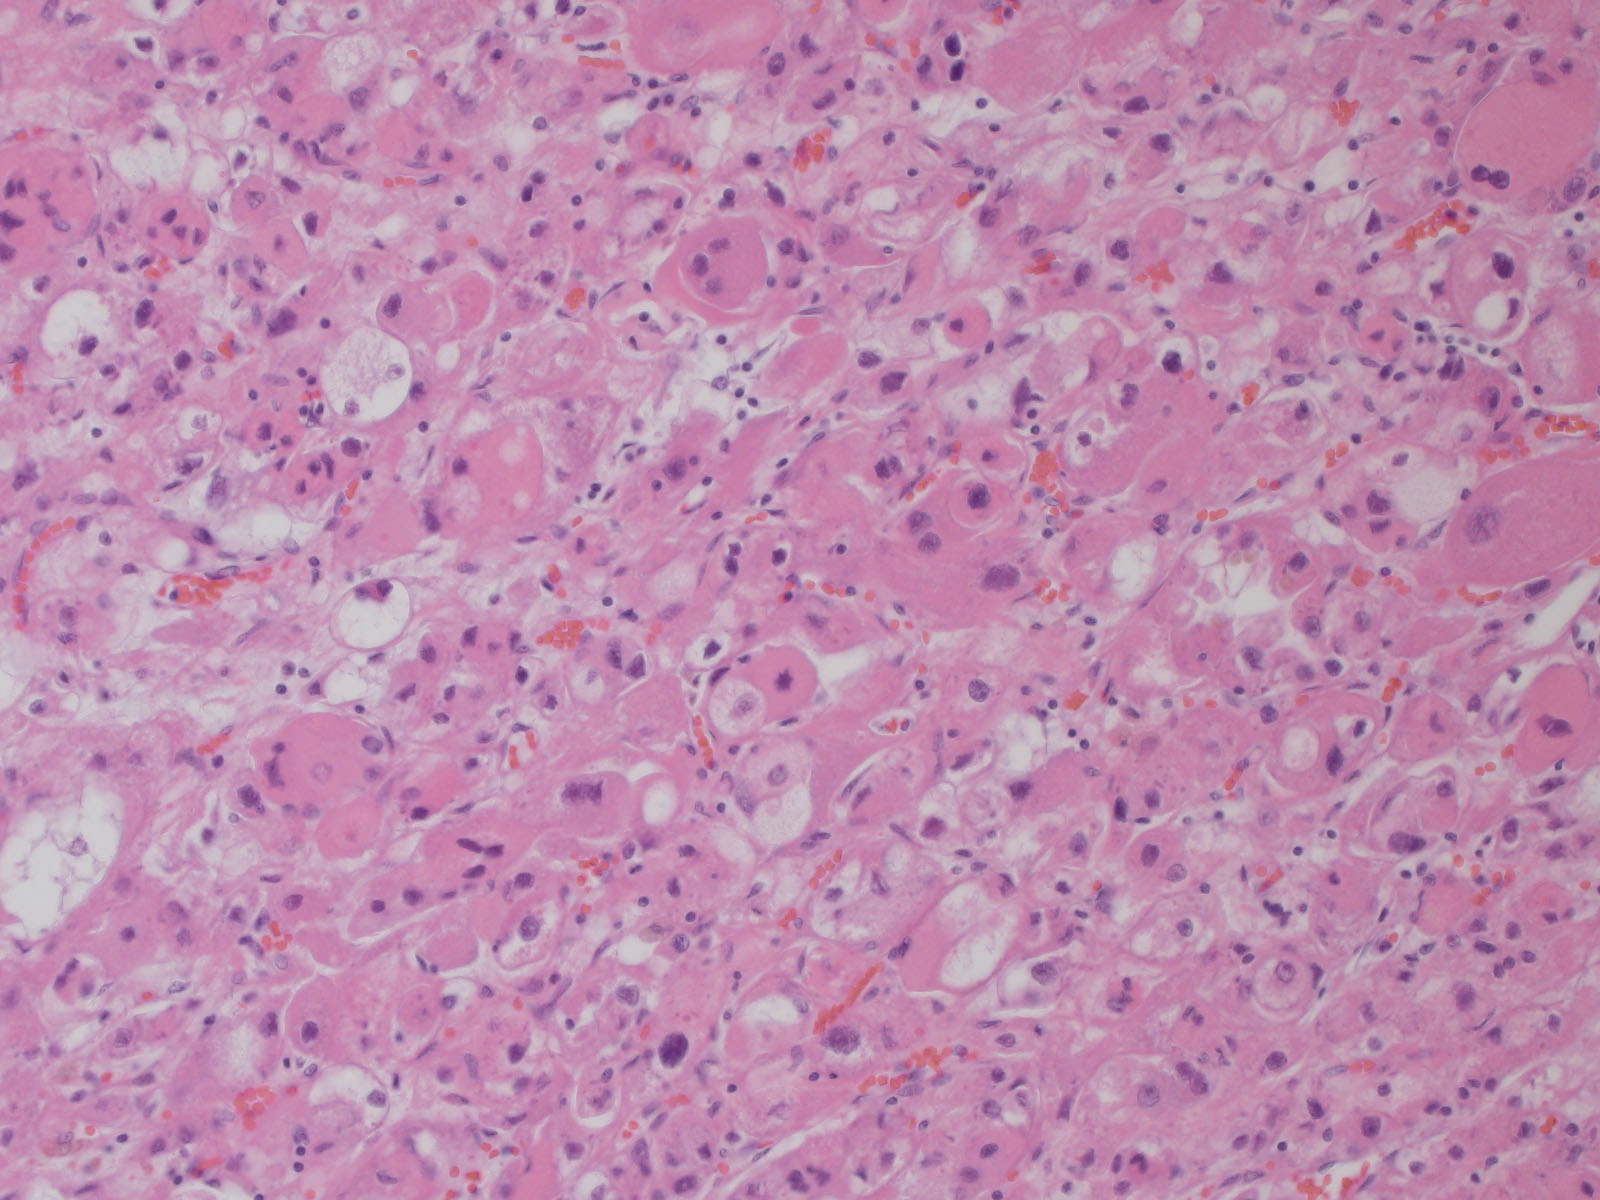

Classification of renal tumors

Case ID: 787